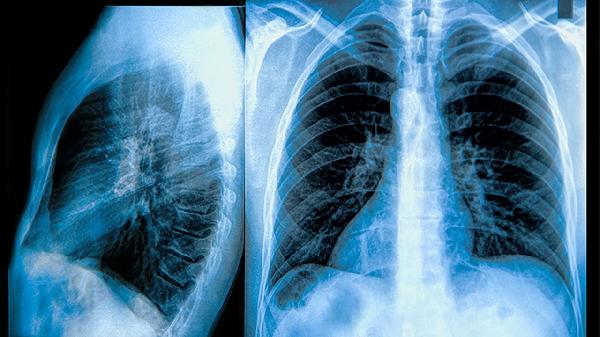

氧分压(PaO2)和二氧化碳分压(PaCO2)的正常值分别是80-100mmHg和35-45mmHg。氧分压反映血液中氧气的含量,二氧化碳分压则反映血液中二氧化碳的排出情况。两者是评估呼吸功能的重要指标。氧分压低于80mmHg或二氧化碳分压高于45mmHg可能提示呼吸系统或代谢异常,需结合具体症状和检查结果进一步诊断。

氧分压正常值为80-100mmHg,低于80mmHg可能提示低氧血症,常见于肺部疾病、心脏疾病或高原环境。二氧化碳分压正常值为35-45mmHg,高于45mmHg可能提示二氧化碳潴留,常见于慢性阻塞性肺疾病(COPD)、呼吸衰竭或中枢神经系统疾病。两者的平衡由肺通气和肺泡气体交换共同维持。